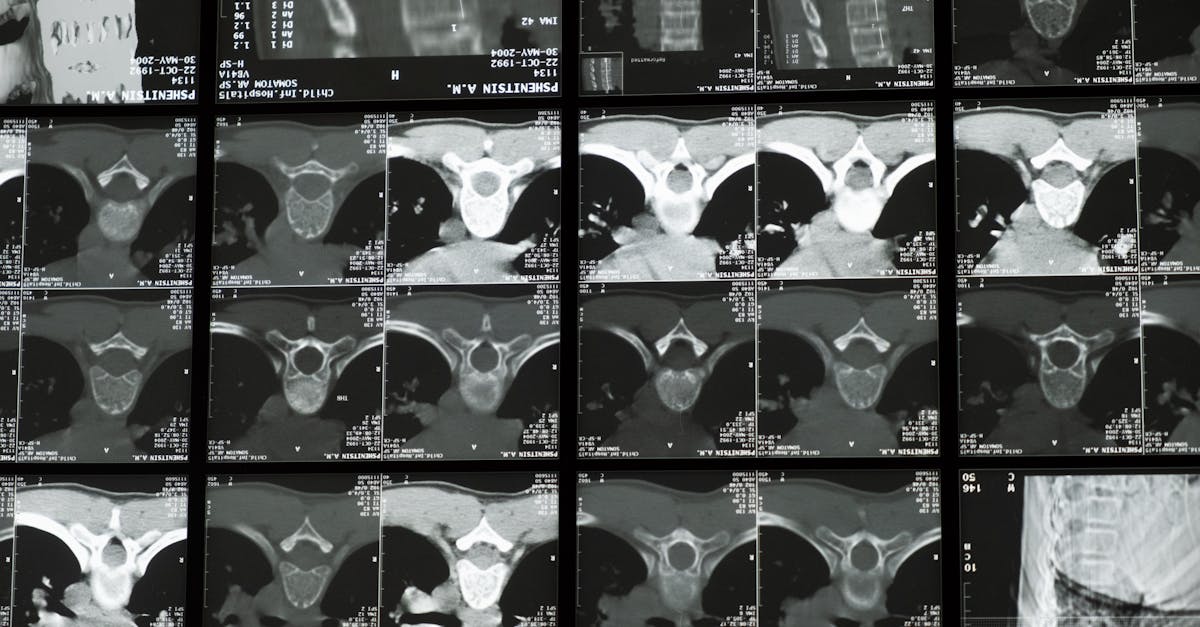

Pain perception is a multi-faceted process influenced by a myriad of factors, both physical and psychological. When magnetic resonance imaging (MRI) results appear normal despite persistent pain, it can be baffling for both patients and healthcare providers. This scenario highlights the intricate nature of pain perception, which can be modulated by emotional states, past experiences, and even social interactions.

Neuroplasticity, the brain's ability to reorganize itself by forming new neural connections, plays a crucial role in the persistence of pain. Chronic pain can lead to alterations in the brain's structure and function, resulting in heightened sensitivity to pain stimuli. Understanding the concept of neuroplasticity sheds light on why individuals may continue to experience pain even when diagnostic tests show no apparent abnormalities. By delving into the complexities of pain perception and neuroplasticity, healthcare professionals can offer more holistic and tailored approaches to pain management.